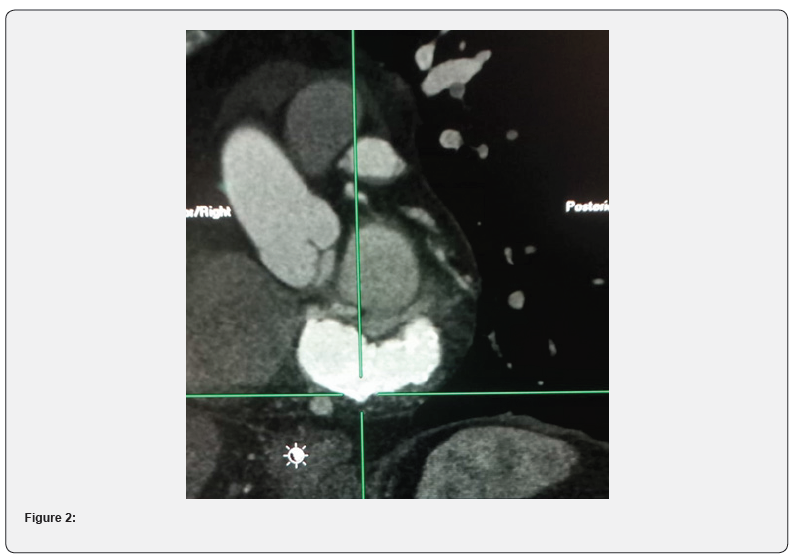

Patient underwent a cardiac CT with and without contrast medium that revealed a hyperdense mass located at the anterior and posterior mitral ring, highly suggestive of caseous calcification of the mitral annulus (see Figures 1 and 2). The mass extended circumferentially for about 75 mm with a maximum thickness of 19 mm. In contrast with other cases of mitral calcification there was not an important involvement of valve apparatus. It showed also coronary calcifications with a stenosis around 50% in the second segment of the anterior descendant artery. The patient was asymptomatic for angor or dyspnea, so she was prescribed an ECG-holter and treated conservatively and followed with echocardiography